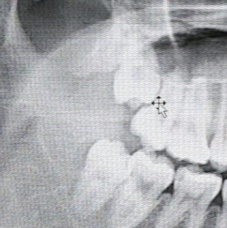

일단 저는 3년 전에 오른쪽에 누워있는 수평 매복 사랑니 하나, 왼쪽 위에 살짝 누운 매복 사랑니 하나, 왼쪽 아래의 매복 사랑니 하나, 오른쪽 위에 그나마 제대로 나온 사랑니 하나를, 크기가 커서 마취하고 두 조각으로 쪼개서 고통 없이 뽑고 멀쩡하게 살아있습니다

: 저는 전문가는 아니지만, 사랑니를 발견한 그 즉시 병원과 상담 후에 뽑는 게 좋다고 생각합니다. 제가 사랑니의 존재를 13살때 충치치료도 하고 검진도 받으면서 알게 됐는데, 그때도 매복 수평 사랑니였습니다. 이게 치열에 어떤 영향을 미칠지 모르고 그냥 성인이 될 때까지 두고 23살에 뽑았는데, 누워있던 사랑니가 자기가 자랄 자리를 고르게 자란 치열을 압박시켜서 치열이 좀 비뚤어졌습니다. 저는 교정을 한 적이 없는데 교정했냐는 소리를 종종 듣는데, 만약에 사랑니가 없었다면 더 고르게 자란 치열을 가질 수 있었을 겁니다... 게다가 매복 수평 사랑니 바로 앞에 있는 어금니 하나는 뿌리가 사랑니에 눌려서 어금니도 누워있습니다.